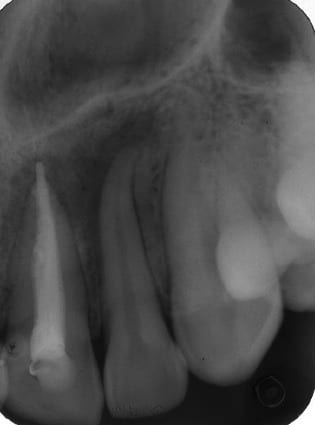

Endos sur 13-12 faites il y a 1 mois suite a un abcès avec fistule, mobilité ++++ des 2 dents, grosse image apicale, endos qui se sont droulés sans problème en condensation latérale, pas de radio contrôle faites ce jour là

j'ai revu aujourd'hui, mobilité nulle, gencive tiptop, plus de problèmes, je refais une radio contrôle et vois ça....

Oui en effet pour un cas comme ca j'attend 3 mois et apres j'opere avec une resection apicale si je n'ai pas de probleme au sondage parodontale .

Pour moi un "vieux" granulome , surement avec une parois kystique

de volume relativement important

avec un corps étrangé dans la lésion ( ton dépassement )

sont autant de motifs pour ne pas attendre 1 an une potentielle guerison.

J’aurais aimé pouvoir compter sur quelques tests pulpaires au préalable ( sur la canine et sur la latérale), mais, à vue d’œil , en admettant que les deux dents ne répondaient ni au test thermique ni au vitalomètre, il y a possibilité que ce soit peut être une nécrose au niveau de la latérale, de la canine (j’en doute) et un kyste fissuraire latéral concomitant. Ne le penses tu pas? Le site pour un tel kyste est le bon et les deux dents semblent refoulées par la lésion. Peut-être n’as tu réglé que la moitié du problème en ne faisant que l’endo ?

A mon sens la paro aurait aussi à être gérée dans ce cas ...

Le tartre est toujours là : réservoir à microbes.

L'entièreté du problème n'est pas "endo-paro" comme le montrent les radios, etc...

Une partie du problème a été traité par l'endo ...une partie du problème a été résolue ... CQFD ...